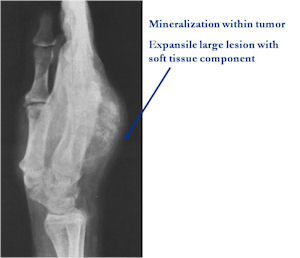

Plain X-rays:

- Geographic, circumscribed lesion usually around 5cm in size.

- There may be expansion of bone, cortical thinning and cortical breakthrough. A soft tissue mass may accompany this lesion but the soft tissue component is usually contained by the periosteum.

- The periosteum remains intact around the soft tissue component. Might need a CT scan to detect the subtle calcification (Egg Shell Rim of Calcification) associated with an intact periosteal reaction

- The lesion may be entirely radiolucent but usually shows some degree of mineralization. Mineralization may appear stippled like cartilage but do not see chondroid pathologically. Mineralization is sometimes better detected on a CT scan rather than an x-ray.

- Usually less surrounding sclerosis than an osteoid osteoma.

- Arise from the Diaphysis (75%) more commonly than Metaphyseal (25%)

- 4 cm to 6 cm in size